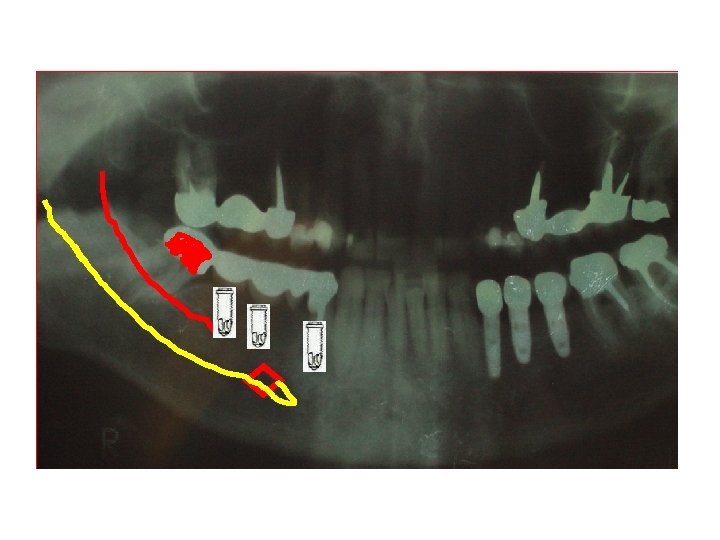

ROMPIMENTO ALVEOLAR INFERIOR TEMPLATE PRÉ-OPERATÓRIO – SOBRE PANORÁMICA P 11 MAGNIFICAÇÃO REGULAR DE 30%